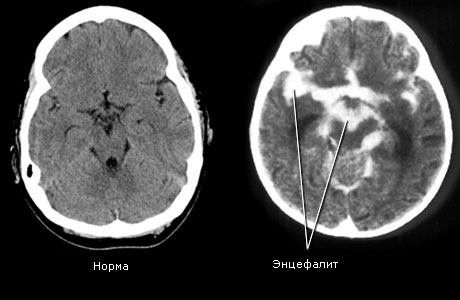

Поражение головного мозга при энцефалите

G04.0 Острый диссеминированный энцефалит